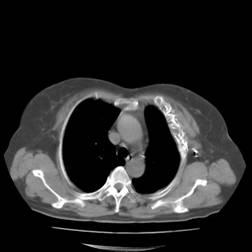

典型病例2:患者张XX,男,65岁,住院号:496686,因发热、胸闷、背痛2月余入院,体温最高达39℃,背部疼痛难忍。2015年6月29日胸部增强CT示:右肺下叶11.6cmx12.5cm巨大肿块,中心大片低密度坏死区,第8胸椎及右侧第8后肋骨转移。于7月2日行CT引导下穿刺活检术,病理证实为右肺鳞癌。给予125I放射性粒子植入治疗,术中首先利用植入针,穿刺肿块中央坏死区,连接引流袋后抽出肿瘤内坏死液体约500ml,抽液后肿瘤缩小约1/3;随后将125I粒子植入到第8胸椎体及第8后肋骨转移区,同时重点放置患侧滋养动脉供血区域。术后第二天,患者体温恢复正常;术后一周随访,患者背痛缓解。该患者出院回家,仍在随访中。

术前CT片